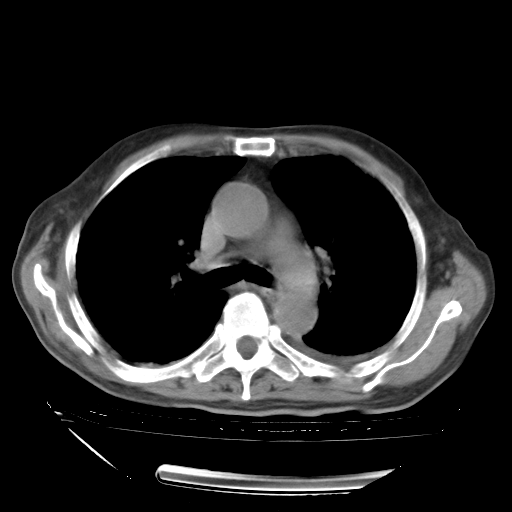

甲强龙80mg/日+抗结核治疗(异烟肼+利福霉素+乙胺丁醇)10天。复查肺部CT。

治疗10天肺部CT